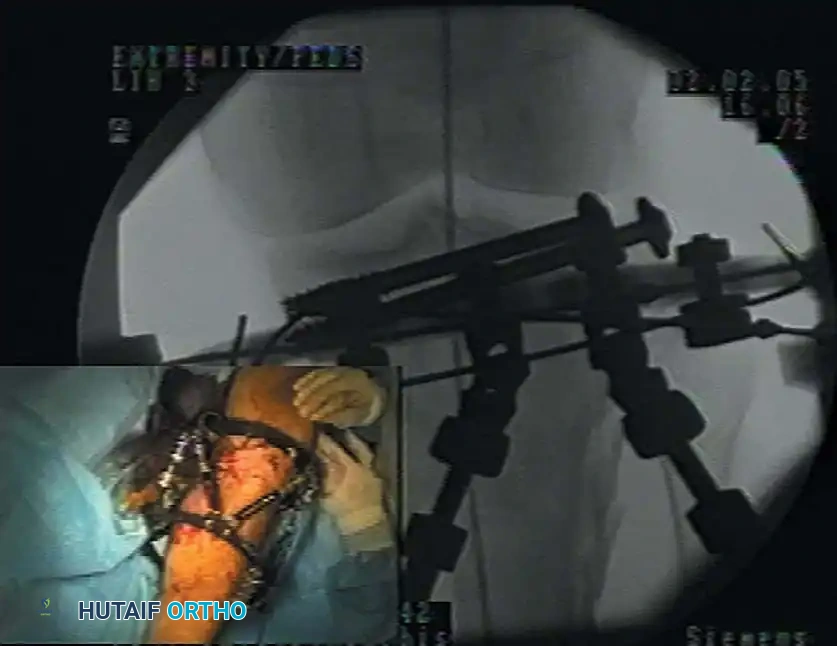

Fig. 50-43 Application of spatial-frame external fixator with use of image intensification. This modality is frequently utilized for the management of infected nonunions following hardware removal.